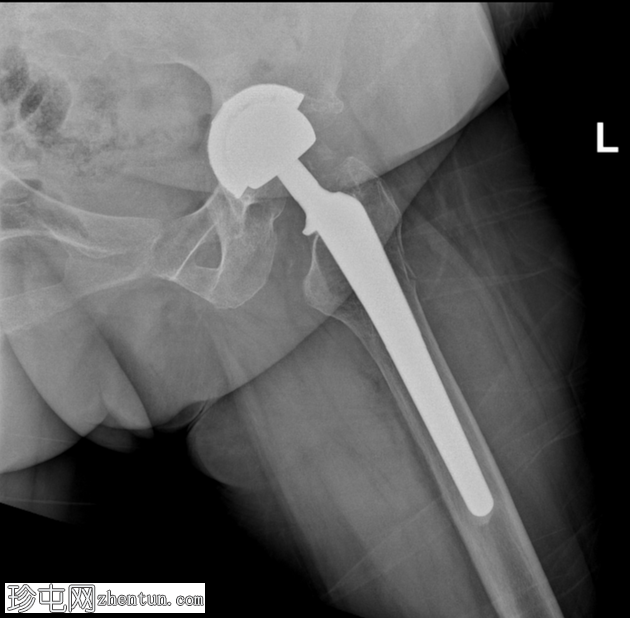

矢状位片

8.jpg

矢状位骨窗

左侧全髋关节置换术。大转子基底部可见轻微移位的假体周围骨折。

大转子滑囊积液,可见脂肪-液体平面。

股骨大转子滑囊扩张并伴有脂肪-液体平面提示创伤性脂肪血肿。